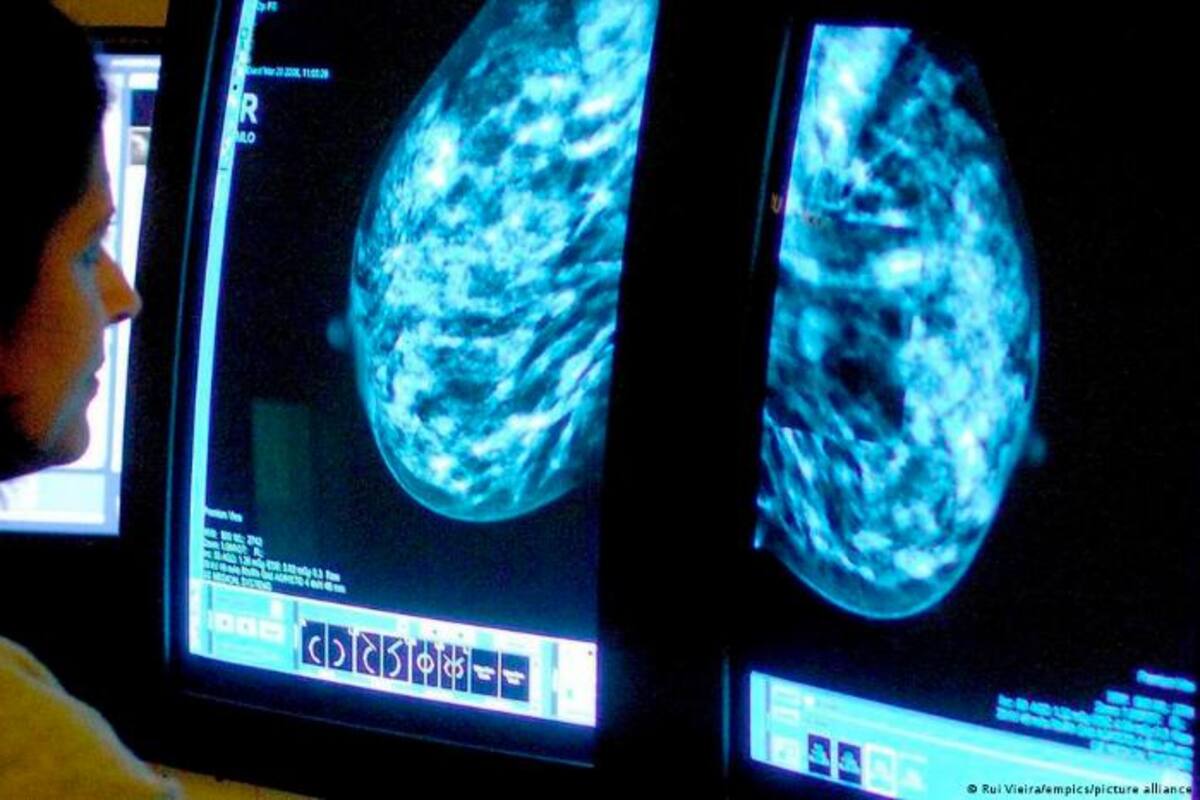

Las mujeres deben someterse a pruebas de detección del cáncer de mama cada dos años a partir de los 40 para reducir el riesgo de morir por esta enfermedad, según recomendó el Grupo Especial de Servicios Preventivos de EE. UU. (US Preventive Services Task Force), un grupo independiente de expertos que recibe financiación federal.

La nueva directriz se basa en una revisión de pruebas y en un estudio de simulación publicado en la revista Journal of the American Medical Association, los cuales vienen a completar un proyecto de recomendación propuesto el año pasado: “Cada vez son más las mujeres de 40 años que padecen cáncer de mama, y las tasas aumentan aproximadamente un 2 % cada año, por lo que esta recomendación supondrá una gran diferencia para todo el país”, declaró en un comunicado la presidenta del Grupo Especial, Wanda Nicholson.

“Empezando a examinar a todas las mujeres a los 40 años, podemos salvar casi un 20% más de vidas”, añade.